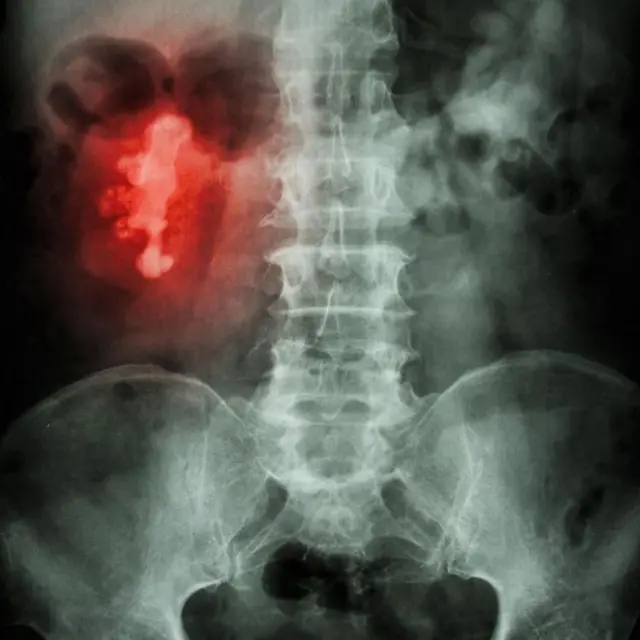

पथरी असामान्य आकार के भी हो सकते हैं. लेकिन अगर किडनी के कनाल (कैलिसेस) के ब्रांच के भीतर पथरी बनना शुरू हुई तो ये हिरण के सींग का आकार भी ले सकती है. इसे स्टैगहॉर्न कैलकुलस कहा जाता है.

इमेज स्रोत, Getty Images

किडनी में होने वाली पथरी तब परेशानी का सबब बन सकती है जब वो यूरेटर्स के रास्ते यानी किडनी से ब्लैडर तक पेशाब लेकर जाने वाली दोनों नलियों में से किसी का रास्ता रोक दे.

अगर ऐसा हुआ तो व्यक्ति को पेशाब करने में तो दिक्कत आती ही है, उसके पीठ के निचले हिस्से में भी गंभीर दर्द हो सकता है.

इस वजह से किडनी के आसपास पेशाब जमा होने लगता है या फिर संक्रमण का ख़तरा पैदा हो जाता है.